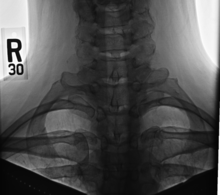

A cervical rib in humans is an extra rib which arises from the seventh cervical vertebra. Sometimes known as "neck ribs",[1] their presence is a congenital abnormality located above the normal first rib. A cervical rib is estimated to occur in 0.6% (1 in 150 people)[2] to 0.8%[3] of the population. People may have a cervical rib on the right, left or both sides.[4]

On imaging, cervical ribs can be distinguished because their transverse processes are directed inferolaterally, whereas those of the adjacent thoracic spine are directed anterolaterally.[7]